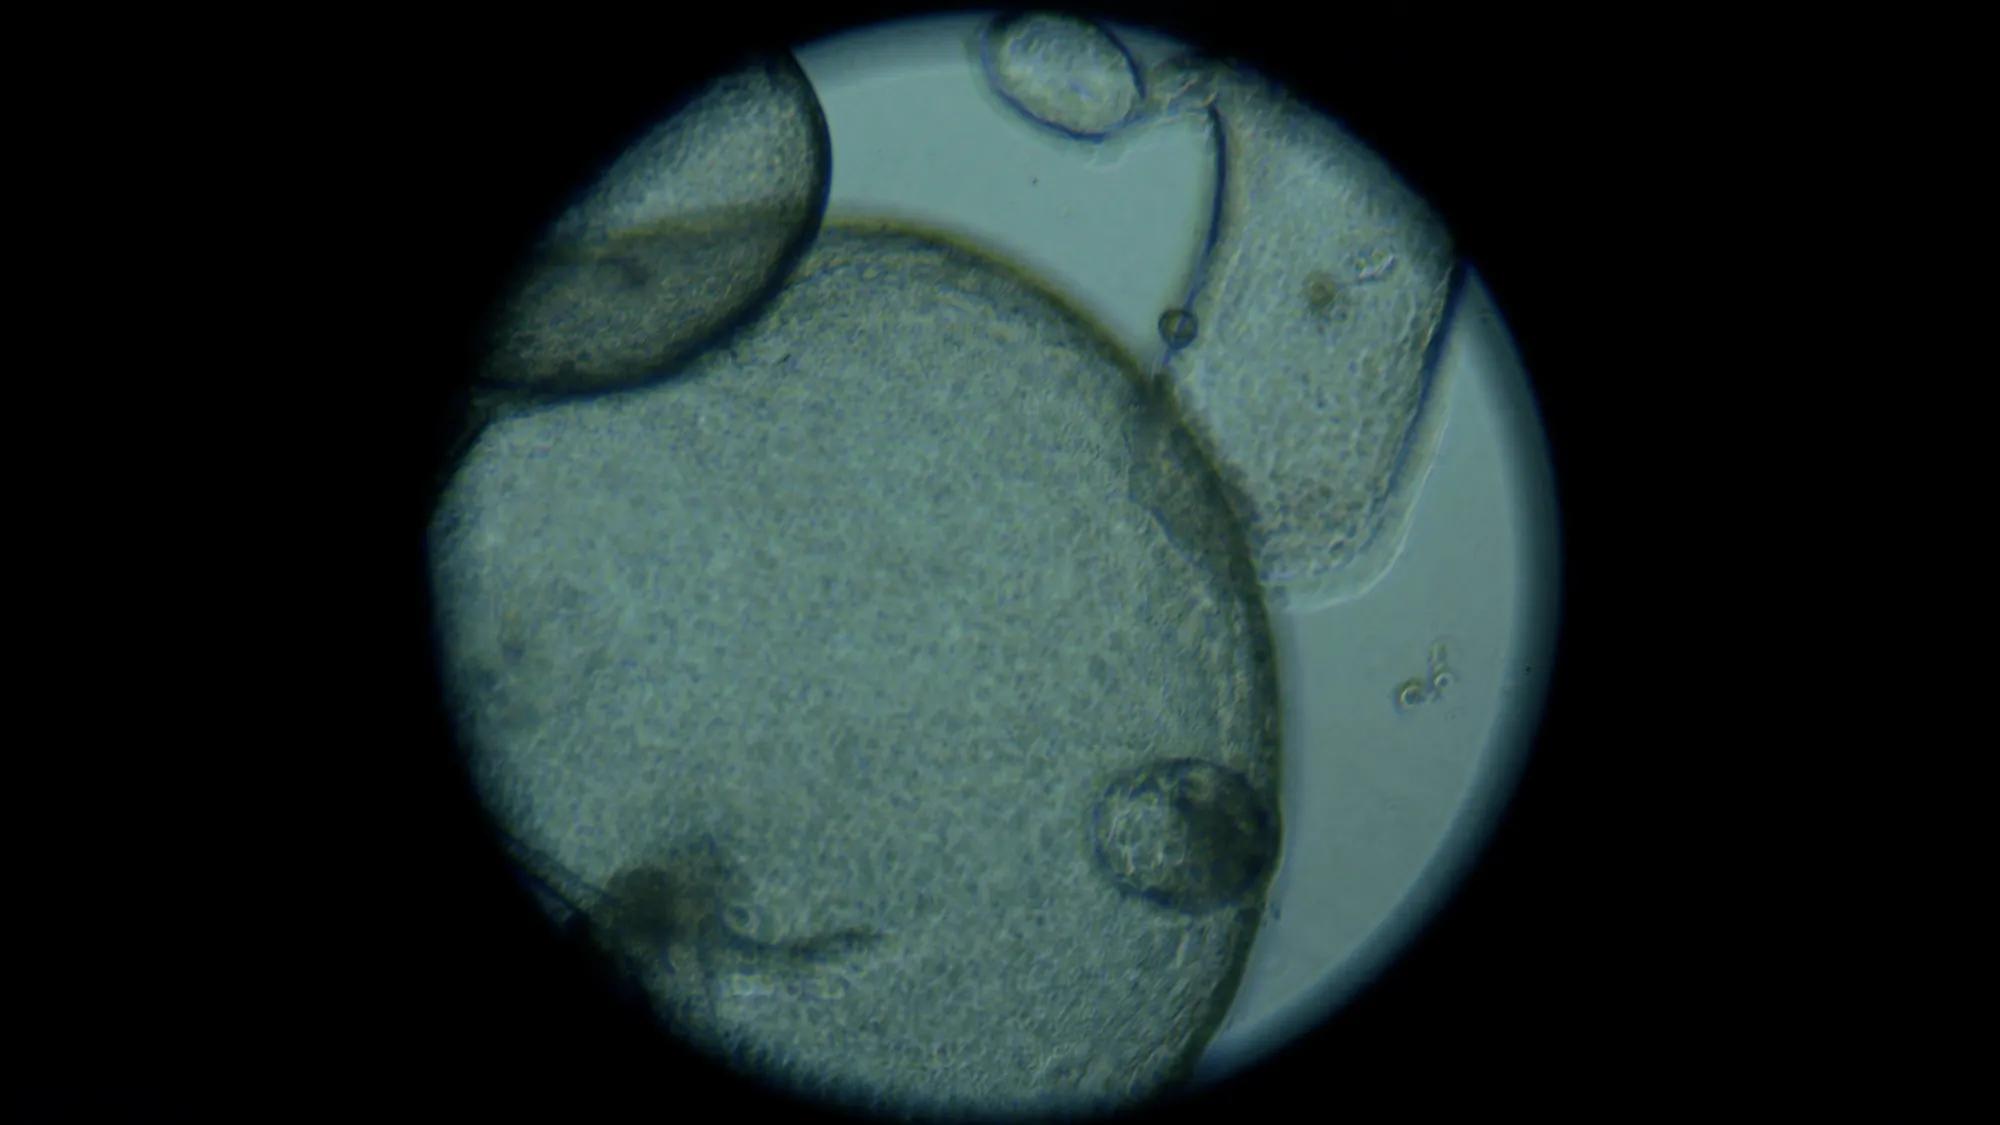

Elise Courtois, assistant professor and director of the Single Cell Biology Lab, leads a team focused on uncovering the fundamental biology of the disease, including why lesions form and spread, what drives recurrence, and how pain develops at the cellular level. Using advanced tools such as 3D tissue models, single-cell sequencing, and spatial ‘omics, her team is mapping the cellular ecosystems within endometriosis lesions. A key area of focus is the interaction between immune cells and pain-sensing nerve cells. This work is helping validate patients’ experiences and pointing toward more targeted therapeutic strategies.